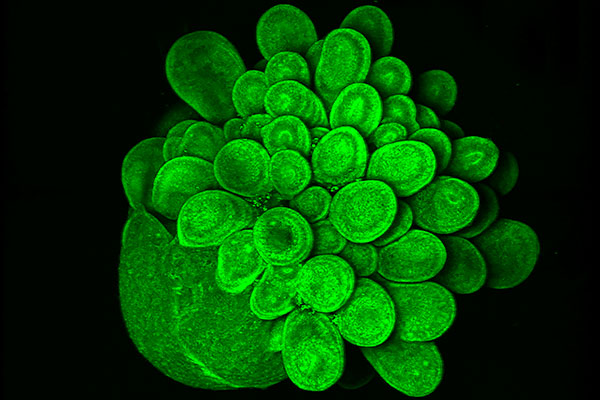

A Blooming Mini Brain

Mariana Oksdath Mansilla

Centre for Cancer Biology

This is an image of a 28 day-old human brain organoid, growing from iPSC that expressed Actin GFP. This 3D culture has a self-organisation of stem cells that mimics the fetal development of the human brain. To culture this organoid, we used a high-content scaffold that we developed in the lab using a 3D printer. The capability to print our high-content device, allows us to test efficiently several scaffold conditions for the growth of human brain organoids. The design of this human brain organoid array that generates healthy cultures (as we can see in the picture), is relevant in the search of a high-throughput platform for the screening of personalised treatment for brain cancer patients.